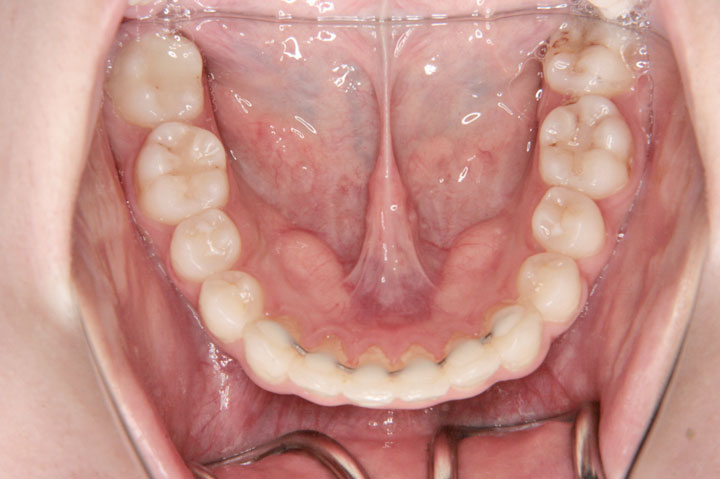

噛み合わせが悪いことを気にされて来院された小学校3年生の女子です。前期治療としてリンガルアーチを用いて上顎側切歯の唇側移動と、ヘッドギアーによる上顎大臼歯の遠心移動を行いました。その後、しばらくの経過観察を経てエッジワイズ装置(デーモンシステム)で後期治療を行っております。非抜歯で良好な結果を得ることができました。